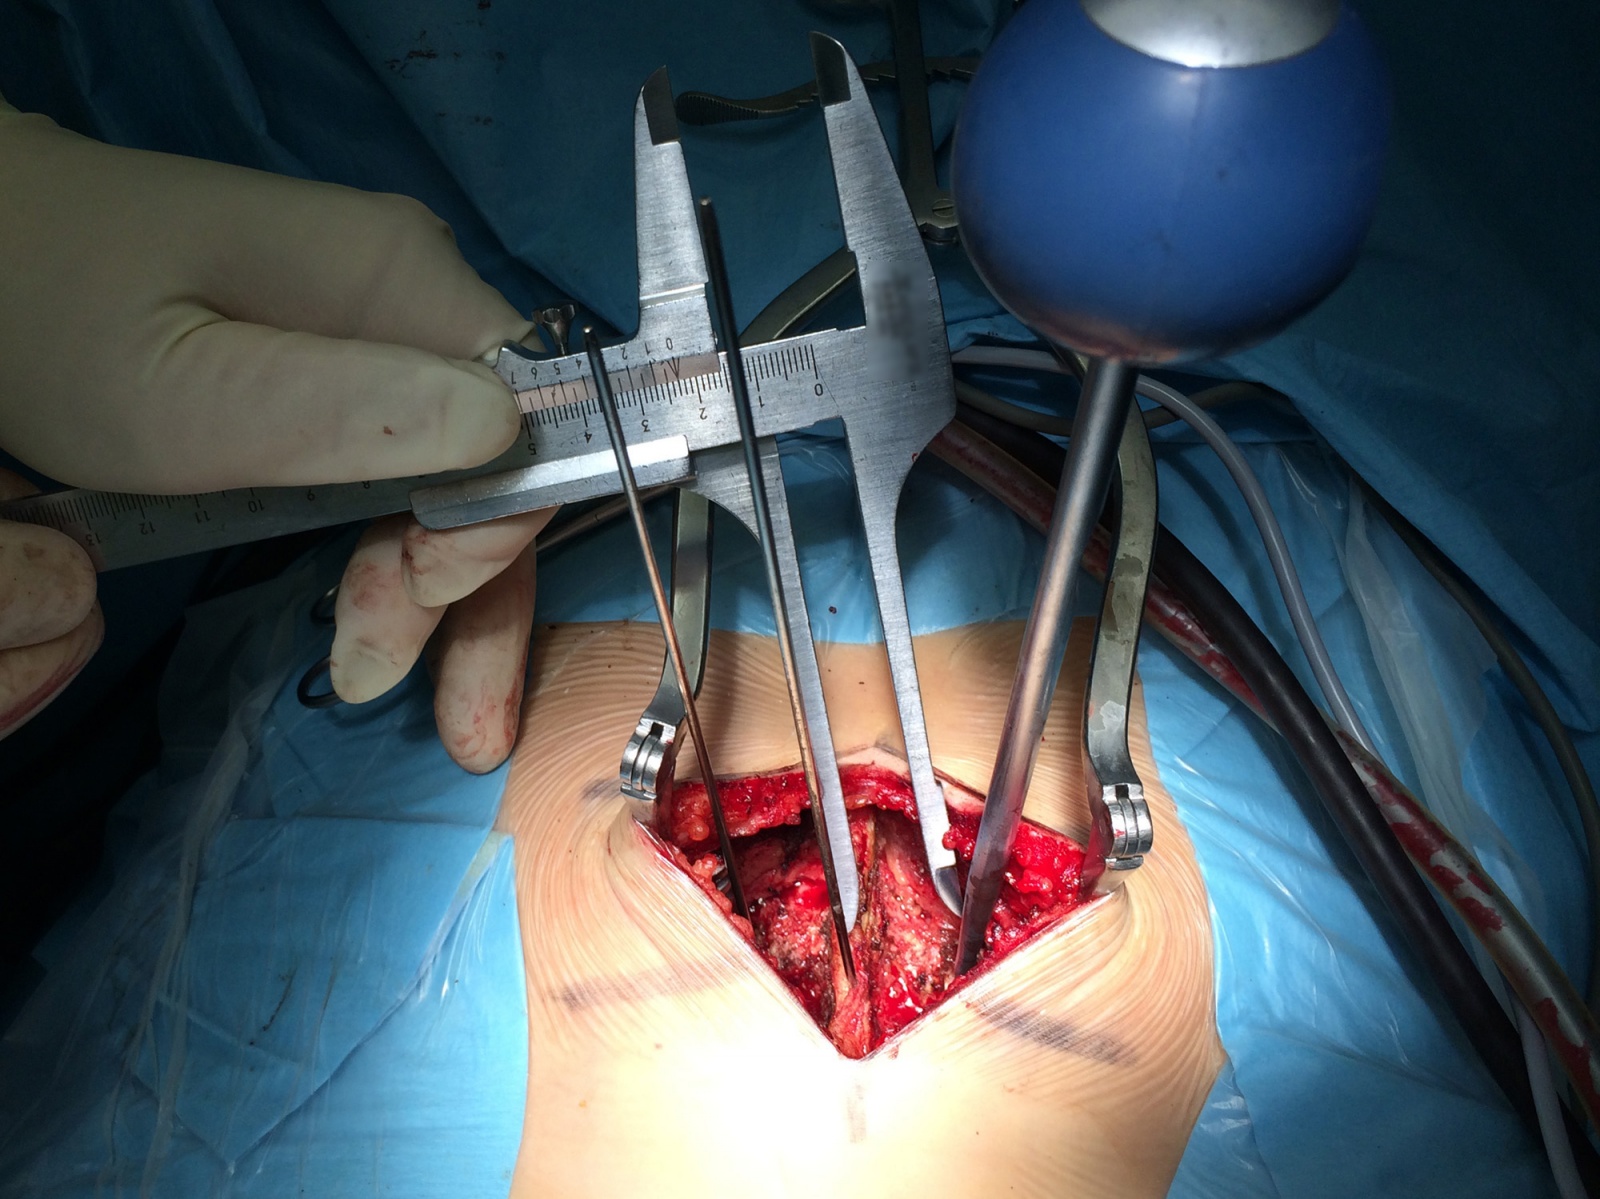

В процессе операции происходит рассечение подкожной клетчатки в области проблемного участка и осуществляется доступ к позвонку. Далее происходит разметка: в соответствии со снимком при помощи штангенциркуля по обе стороны от остистого отростка определяются точки, которые вместе с известными точками введения винтов образуют траектории, по которым контролируется положение инструмента для формирования штифт-канала. Далее происходит сверление и непосредственное введение транспедикулярных винтов.

Измерение расстояния между инструментом для формирования штифт-канала и верхушкой остистого отростка для контроля угла вхождения в аксиальной плоскости